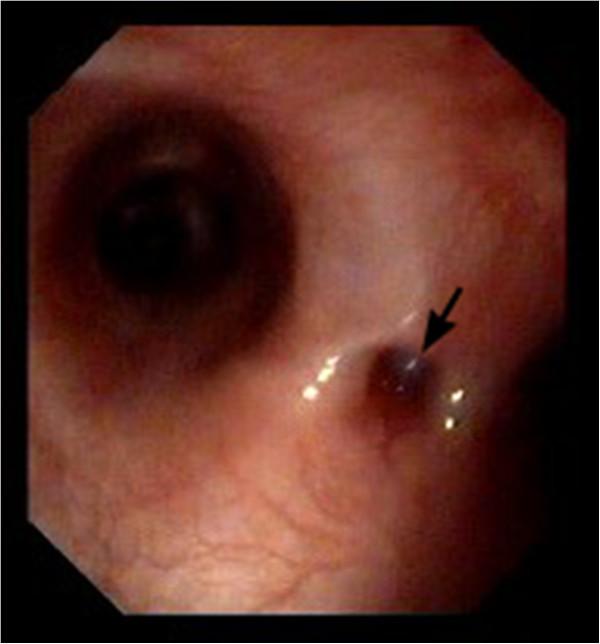

A seven-month-old intact female Spanish Water Dog was presented for further investigation of recurrent respiratory symptom. Bronchoscopy revealed a small hole-like defect in the tracheal wall at the bifurcation. The finding of the contrast material swallow study under fluoroscopy was indicative of a TEF. To further evaluate the connection between the trachea and esophagus, a computed tomography scan was performed. The TEF was surgically approached by thoracotomy through the right lateral sixth intercostal space. The fistula was identified, double ligated and divided. Histopathology confirmed the process to originate from the esophagus and to be patent. The dog was re-examined two weeks and ten months after surgery, with no evidence of recurring clinical signs.

Contrast material swallow study using fluoroscopy was the most reliable diagnostic method. Bronchoscopy may allow the fistula to be visualized, but due to a small fistular opening it can lead to a false negative result. Surgical correction by ligation and dividing of the fistula suggests a good prognosis for early diagnosed and operated TEF.